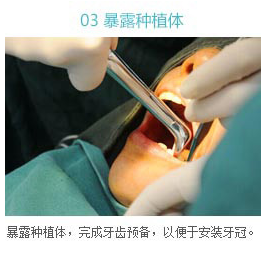

烤瓷牙牙齿矫正

烤瓷牙牙齿矫正就是通过做烤瓷牙的方式来矫正畸形牙。烤瓷牙牙齿矫正是否成功,是跟主治医生的技术是有很大关系的,如果医生操作技术不专业,设计不合理的话,会可能导致烤瓷牙牙齿矫正失败或是烤瓷牙返工等一系列问题。